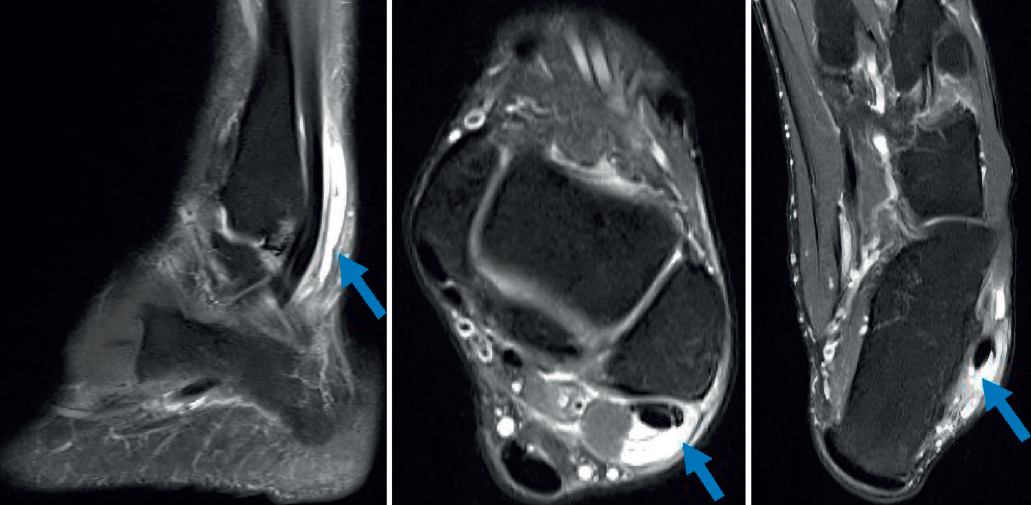

La resonancia magnética (RM) puede mostrar patología concomitante, como una artropatía subastragalina, lesiones osteocondrales del astrágalo, lesiones del ligamento lateral externo, etc. La tendinosis o la tenosinovitis se visualizan mejor en las imágenes en T2 con un aumento de la señal del tendón y líquido alrededor de este (Figura 5). Hay que tener en cuenta que las imágenes de RM pueden presentar el fenómeno del ángulo mágico; esto se da cuando el tendón sufre una angulación de más de 55°, como ocurre distal al maléolo peroneal, y puede dar una falsa imagen de rotura(21). La obtención de imágenes del tobillo en flexión plantar puede aumentar la precisión del estudio, al separar los tendones peroneos en la vaina y disminuir el efecto del ángulo mágico(9).